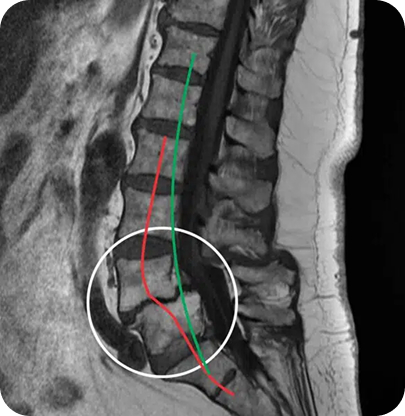

SLIKA MAGNETNE RESONANCE (MRI) - SPONDILOLISTEZA

Zdrs zgornjega vretenca naprej optimalne linje (zelena črta).

Degenerativna spondilolisteza se običajno pojavi na eni od dveh ravni ledvene hrbtenice: raven L5-S1 (spodnji del ledvene hrbtenice, kjer se najpogosteje pojavi) in raven L4-L5.